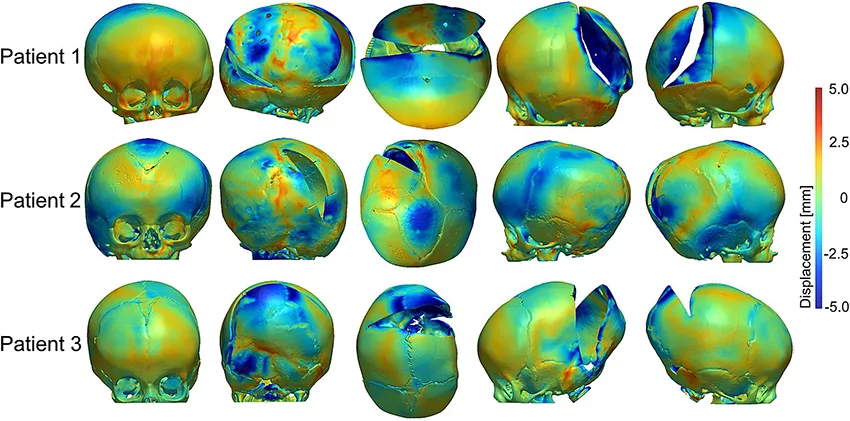

使用未受手术影响的前鼻棘点和额颧缝处标志点获得体积配准后,在 Simpleware CAD 模块对扩张的FE颅骨模型和术后 CT 重建颅骨进行表面偏差分析。然后通过调整参数以考虑每个模型中整个颅骨的平均负和正的表面偏差,使用热 FE 模型迭代地进行模拟。

重建的颅骨模型展示了术前 CT 时的颅内腔形态,对三名患者的模拟结果进行对比。FE 模型和从 CT 获得术后颅骨模型的分析显示额骨和颞骨的表面偏差率相对较低,在被弹簧扩张的后颅骨上表面偏差增大。

本研究能够基于机械效应,比较术前 CT 成像、手术干预和术后干预,探讨颅缝早闭中颅骨生长模式的复杂性,并通过术后 CT 图像重建验证模拟结果。获得的模拟结果表明,手术后颅骨的最终形状取决于实施的截骨术,相对较长的切口主要导致颅骨中的铰链和扩张,而最小的切口会使截骨边缘之间的间隙扩大。因此,通过依据患者个体化图像数据的研究更好地理解截骨大小和位置是至关重要的。